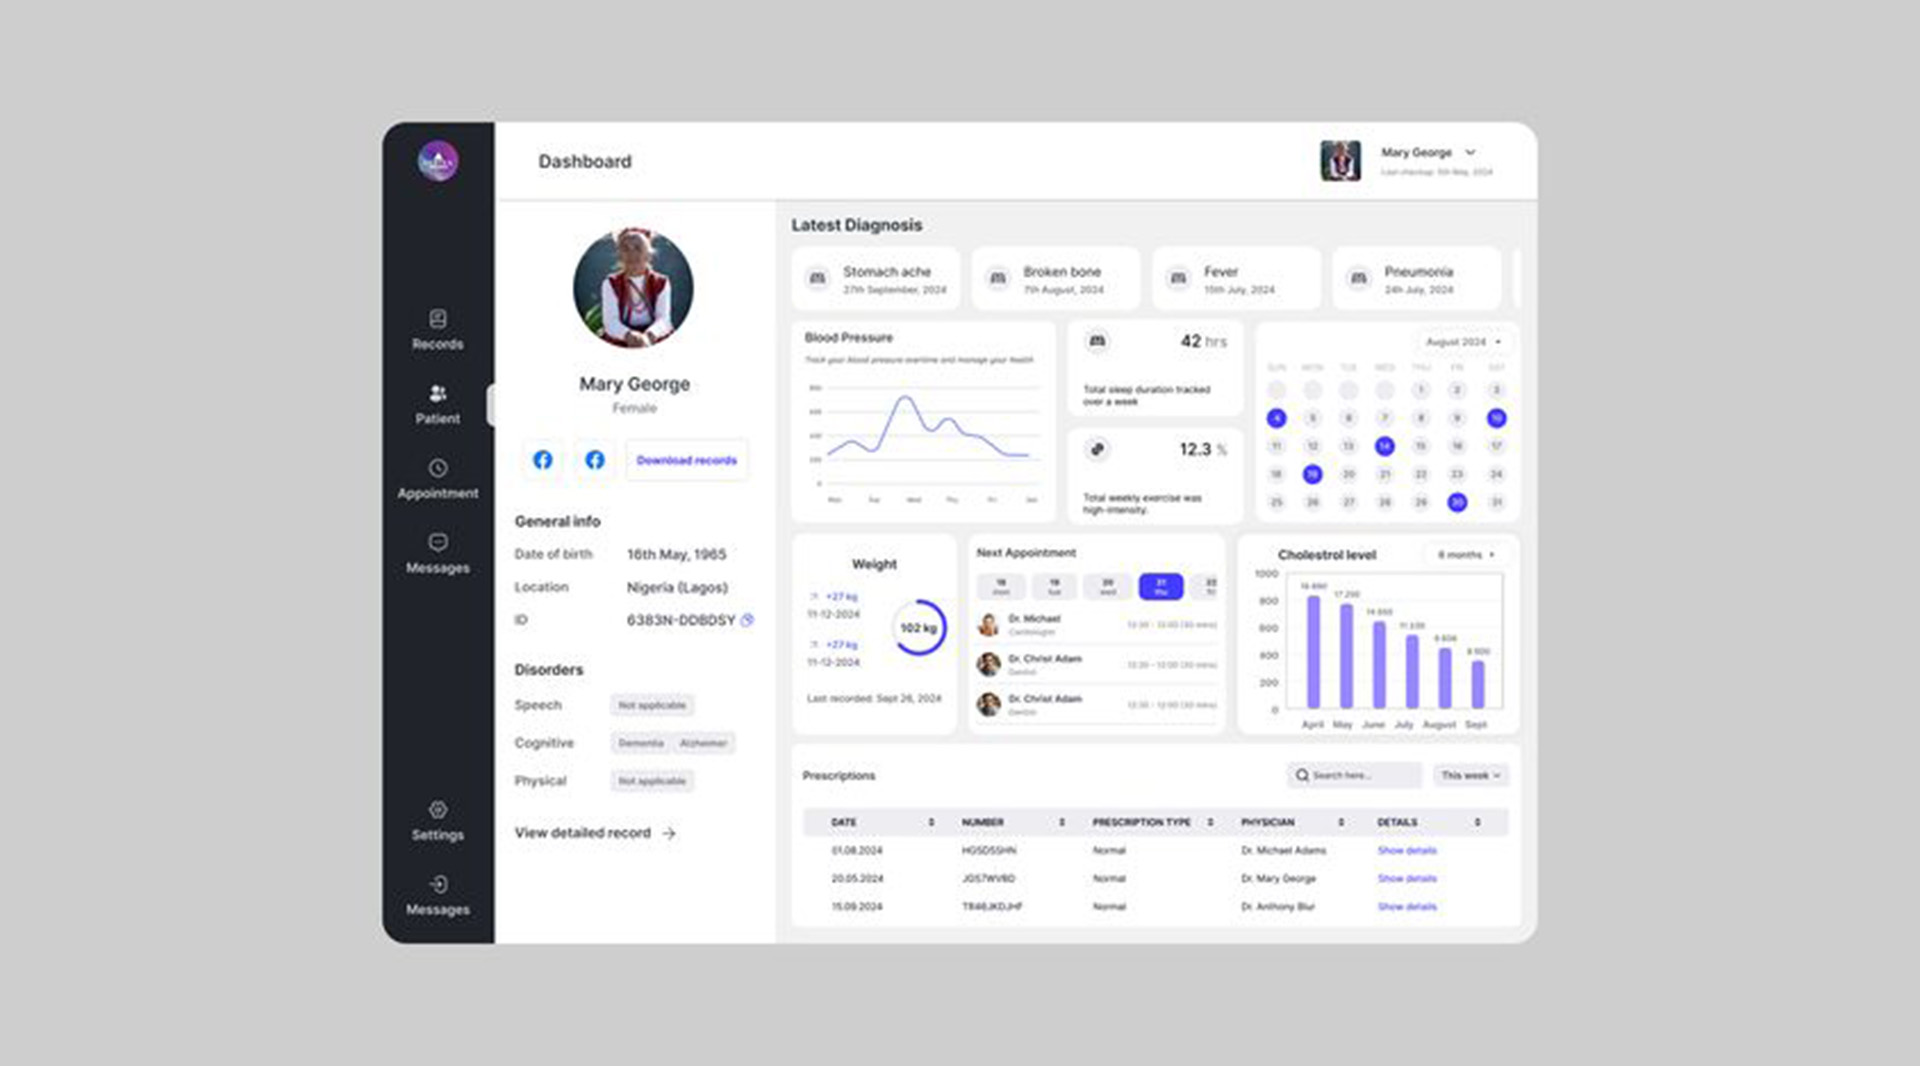

From healthcare to e-commerce, every interface we

design is built around real people and their real-world needs.

Bespoke Software UI/UX Design – Starts at $2000

- Tailored UI/UX design for complex software like CRMs, admin panels, dashboards, or internal tools

Includes user flow mapping, wireframes, high-fidelity UI for up to 20 screens

Figma-based design system, responsive layout support, and dev-ready assets